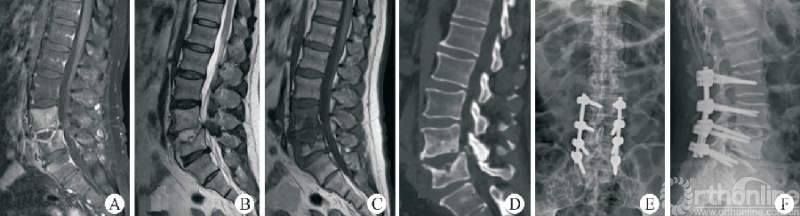

1.4 OLIF 技术用于治疗腰椎感染性疾病

脊柱结核、化脓性脊柱炎等脊柱感染性疾病是脊柱外科的常见疾病,经正规保守治疗无效之后常需要外科手段的介入。经典的前路技术虽然效果确切,但因其手术创伤大、技术难度高等特点而难以在临床广泛展开。通过侧前方入路对脊柱感染部位进行彻底清创,以自体髂骨行植骨融合,联合后路钉棒系统内固定也是有效的治疗腰椎结核的手段(图3)[23-24]。

图3 OLIF技术治疗腰椎结核

相较于ALIF组,OLIF技术用于治疗腰椎结核具有出血量少、微创、并发症少等优点。WANG等[25]通过对14例脊柱感染患者经OLIF技术清创、取髂骨植骨融合的疗效分析证实,对于金黄色葡萄球菌、布鲁氏菌、肠杆菌等引起的腰椎感染,OLIF技术均是有效且安全的治疗手段。TONG等[26]经过长期随访也证实,OLIF技术联合后路钉棒系统内固定是治疗抗生素无效的单节段自发性化脓性腰椎间盘炎的有效方案。因此,对于抗生素治疗无效的腰椎感染性疾病,OLIF技术是一种微创、有效的解决方案。